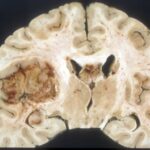

I ricercatori dell’Università di Sheffield hanno scoperto un nuovo percorso di terapia genica con un importante meccanismo di regolazione per mantenere sano il nostro genoma. Questo percorso ha il potenziale per proteggerci da gravi malattie che limitano la vita come il cancro e la demenza.

Il cancro e la neurodegenerazione sono due importanti sfide per la salute che attualmente colpiscono la popolazione e costituiscono due facce della stessa medaglia: uno è causata da una proliferazione cellulare incontrollata dovuta a danni al genoma e l’altra è causata da un danno eccessivo al genoma che causa la morte cellulare. Questo nuovo percorso ha un impatto su entrambi e offre nuove opportunità terapeutiche per aiutare a combattere le malattie.

Pubblicata su Nature Communications, la ricerca ha scoperto che quando le cellule del nostro corpo leggono il DNA per costruire proteine, spesso commettono errori che possono danneggiare il nostro genoma, causando malattie come il cancro e la demenza. Tuttavia, studiando come le cellule riparano i danni nel DNA per mantenerci sani, gli scienziati hanno scoperto i vantaggi di tre proteine ​​che lavorano insieme come una squadra. Le tre proteine, chiamate USP11, KEAP1 e SETX, ricevono istruzioni dal loro coach per dirigere la loro funzione nello spazio e nel tempo con notevole armonia, per mantenere sano il nostro DNA.